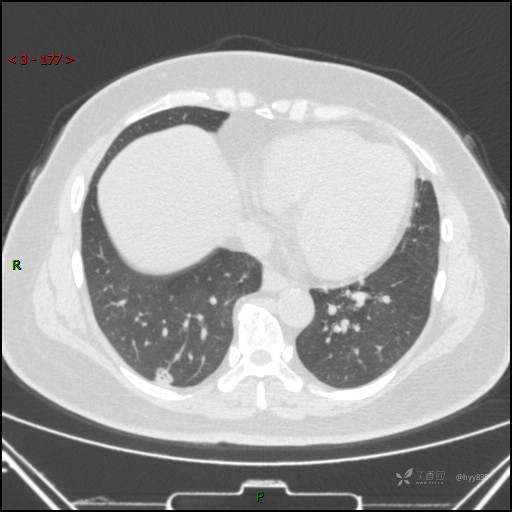

51岁/F,体检发现肺结节,又见“鬼脸”,增强也有特点,请分析---结果公布~

简要病史:体检发现右下肺结节,来我院行进一步增强检查并手术

胸部CT平扫